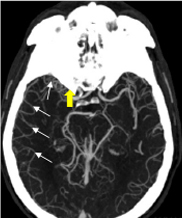

A non-contrasted CT scan of the brain is ordered for the patient. Results are shown in Figure 1.

Figure 1. Non-contrasted CT brain scan of the patient.

A hyperdense artery sign is a finding that can be seen quickly on non-contrasted CT brain scans without performing angiography (Figure 2). This sign has been shown to be up to 95% specific and 52% sensitive for detecting intraluminal thrombus and, therefore, arterial occlusion.4

Figure 2. The yellow arrow points to the hyperdense artery sign at the terminus of the right internal carotid artery and extended into the middle cerebral artery on the patient’s non-contrasted CT brain scan (Figure 1).